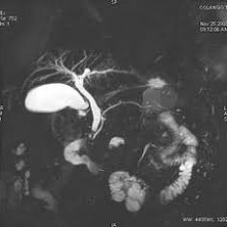

Resonancia nuclear magnetica de vias biliares. EN. Codigo 883430 (2022)

ESCANOGRAFIA NEUROLOGICA S.A.

Medellin, Barrio Prado Centro: Calle 59 # 50 A - 14

Sabaneta, Carrera 48 # 50 sur 128. Al interior del Centro Comercial Mayorca Mega Plaza